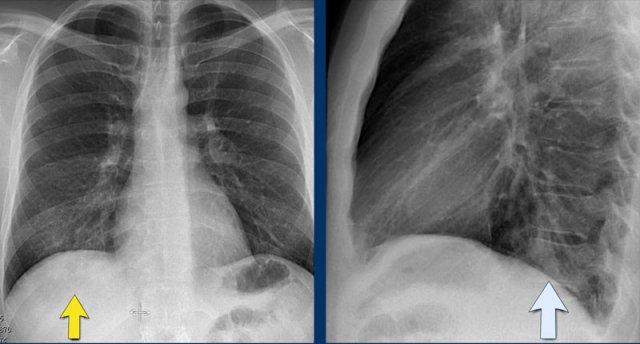

Case Example: Subtle Signs of Congestive Heart Failure

Begin by reviewing these current chest radiographs.

Based solely on these images, one might suspect congestive heart failure (CHF), though the findings are subtle.

Now review the previous study…

Scrolling between the current and prior films significantly increases diagnostic confidence in your diagnosis of congestive heart failure.

Key comparative findings include:

• Cardiac size: Slightly increased compared to the previous study; however, cardiomegaly was already present.

• Pulmonary vasculature: Mild vascular engorgement suggesting elevated pulmonary venous pressure.

• Interstitial markings: Subtle signs of interstitial edema .

• Pleural effusions: Bilateral small effusions, with subtle changes in the inferoposterior borders of the lower lobes, suggesting fluid accumulation.